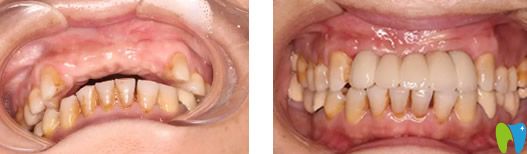

看看路女士在成都新橋口腔種牙前后效果對比圖:

重獲“新牙”的路女士高興極了,她終于擺脫了假牙,可以像從前一樣大膽吃東西、自信講話了,再也不怕假牙掉出來,也不用因?yàn)榧傺离y堪了!